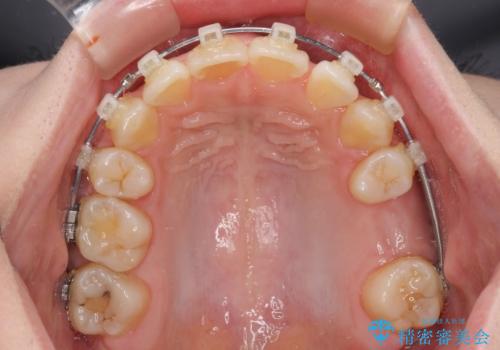

- 奥歯の欠損と、抜歯矯正の後戻りを気にして来院された患者様です。

上下前歯をワイヤー保定していましたが、強い舌の突出癖により上下ともにスペースができ、上下前歯は非接触になっていました。

マウスピース矯正でもワイヤー矯正後でも対応可能でしたが、自己管理の煩わしさからワイヤー矯正後を選択されました。

舌のトレーニングをしっかりと行っていただきながらワイヤー装置により矯正治療を行い、途中でインプラントを埋入し、矯正治療後に補綴治療を行うこととしました。